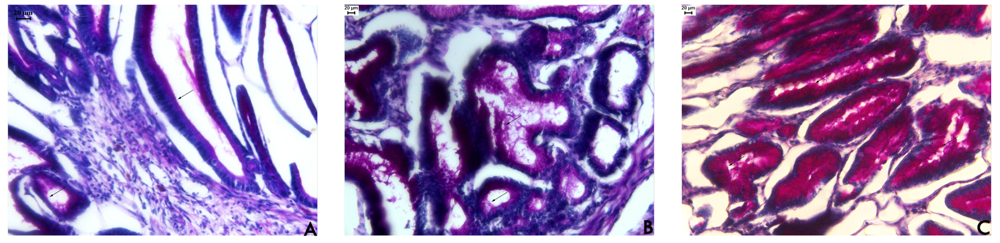

Hayashida et al. [16] observed a notable expression of mucin in regenerating areas in acetic acid-induced ulcers. The mucus bicarbonate barrier is the only pre-epithelial barrier between the lumen and epithelium, and when its breaks down in disease, other intracellular mechanisms come into play [17]. The periodic acid-Schiff (PAS) histochemical method exhibits characteristic carmine staining of stomach regions that secrete mucopolysaccharides. At the end of the treatment period, all stomachs were processed by PAS histochemical analyses. In samples from rats treated with EAF, we observed the intense secretion of mucus in gastric glands (Figure 2) that was absent in sample from the other groups. Mucus production represents one of the main mechanisms of local gastric mucosal defense [17]. A number of factors appear to influence ulcer healing, but mucus and bicarbonate secretion may be important in the ulcer healing process because the mucus/bicarbonate layer protects newly formed cells from acid and peptic injury [18].